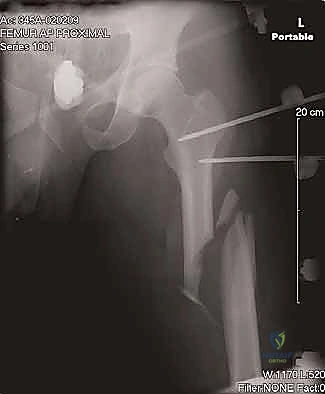

يُطلق مصطلح "الأمامي" (Anterograde) على الطريقة التي يتم بها إدخال المسمار من الأعلى (من جهة الورك أو المدور الكبير) نزولاً باتجاه الركبة داخل القناة النخاعية.

- الاستقرار التدويري (Rotational Stability): يتم تثبيت المسمار بمسامير قفل عرضية (Interlocking Screws) من الأعلى والأسفل تمنع دوران العظم أو قصره.

5. إدخال المسمار النخاعي

يتم إدخال المسمار المعدني بعناية فائقة فوق السلك التوجيهي حتى يعبر منطقة الكسر ويستقر في الجزء السفلي من الفخذ.

6. القفل (Interlocking)

يتم إدخال مسامير قفل عبر المسمار النخاعي من الأعلى (بالقرب من الورك) ومن الأسفل (بالقرب من الركبة) باستخدام أجهزة توجيه دقيقة لضمان عدم تحرك الكسر.